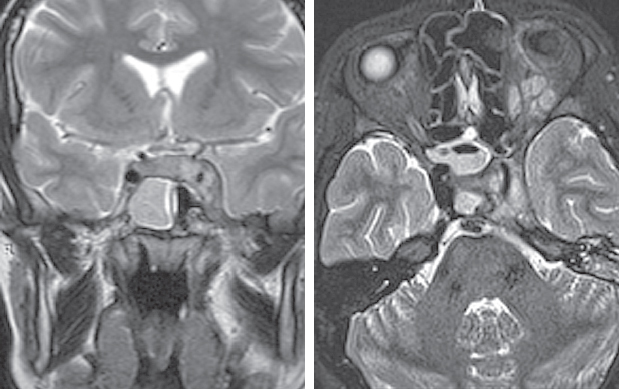

По результатам МРТ головного мозга от 16.06.2021 (рис. 2): МР-признаки подоболочечного скопления жидкости с высоким содержанием белка, воспалительных изменений оболочек в левой лобной области. Картина соответствует субдуральной эмпиеме.

Рис. 2. Магнитно-резонансная томография головного мозга от 16.06.2021: а — сагиттальная проекция в режиме Т2. Прослеживаются воспалительные изменения оболочек в левой лобной области. Картина соответствует субдуральной эмпиеме; b — аксиальная проекция в режиме Т2. Снижение пневматизации левой верхнечелюстной пазухи, пристеночный отек слизистой; c — аксиальная проекция в режиме Т2. Снижение пневматизации клеток решетчатого лабиринта; d — аксиальная проекция в режиме Т2. Воспалительные изменения оболочек в левой лобной области, субдуральная эмпиема

Fig. 2. Magnetic resonance imaging of the brain from 16.06.2021; a – sagittal projection in T2 mode. Inflammatory changes in the membranes in the left frontal region are traced. Picture consistent with subdural empyema; b – axial projection in T2 mode. Decreased pneumatization of the left maxillary sinus, parietal edema; c – axial projection in T2 mode. Decreased pneumatization of cells of the ethmoid labyrinth; d – axial projection in T2 mode. Inflammatory changes in the membranes in the left frontal region, subdural empyema